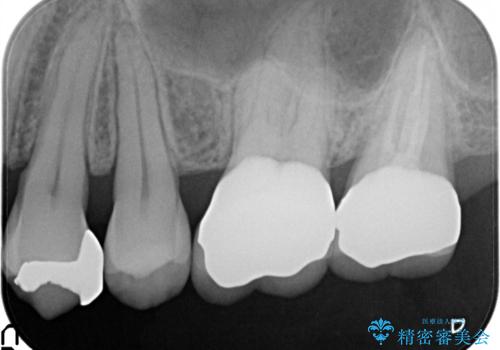

- 矯正の治療後に目立つ金歯を白くしたいとのことで治療することとなりました。

左上の奥歯に大きな金歯と、その後ろの歯が矯正治療用の仮歯が装着されていました。

これらの歯にオールセラミッククラウンを装着することとなりました。